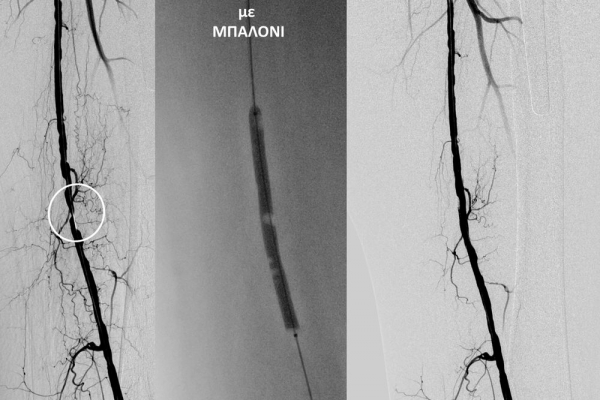

- Η αγγειοπλαστική των αρτηριών είναι μία μη χειρουργική επέμβαση που αποσκοπεί στη διάνοιξη των στενωμένων ή αποφραγμένων αρτηριών. Γίνεται με την ίδια τεχνική όπως και αγγειογραφία. Η αγγειοπλαστική των αρτηριών μπορεί να γίνει είτε με απλή διάνοιξη της αρτηρίας που εμφανίζει στένωση με μπαλόνι ή και να συνοδευθεί από τοποθέτηση ενδαγγειακής πρόθεσης (stent).